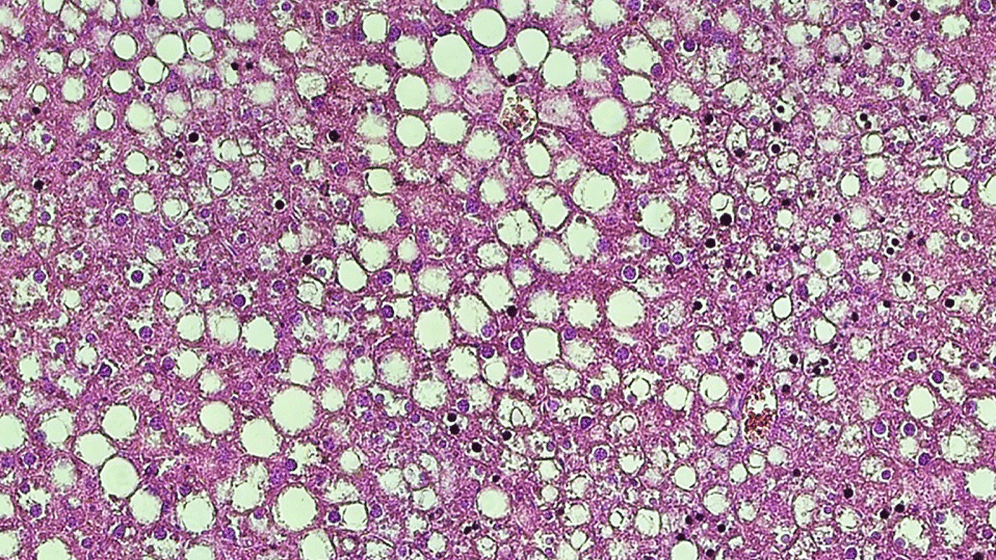

Die MRT-Messungen zeigen, dass das gesamte Gehirn von den hormonellen Veränderungen beeinflusst wird. „Erstaunlicherweise ergaben bei allen vier Frauen die Volumenänderungen des Gehirns über den Zyklus etwa dasselbe Muster der Hirnregionen. Wie sich aber die Hirnstruktur einer bestimmten Region ändert, unterschied sich individuell je nach den hormonellen Bedingungen deutlich“, erläutert die Erstautorin Carina Heller. Bei den Frauen mit typischem Zyklus ist Progesteron maßgeblich für die Schwankungen der Hirnstruktur verantwortlich. Östradiol hingegen ist das dominierende Hormon bei Endometriose oder der Einnahme der Pille und daher bei diesen Frauen für die Schwankungen der Gehirnstruktur zuständig. Damit zeigt sich, dass es nicht immer die gleiche Gehirn-Hormon-Kopplung gibt, sondern diese vom hormonellen Milieu abhängt.